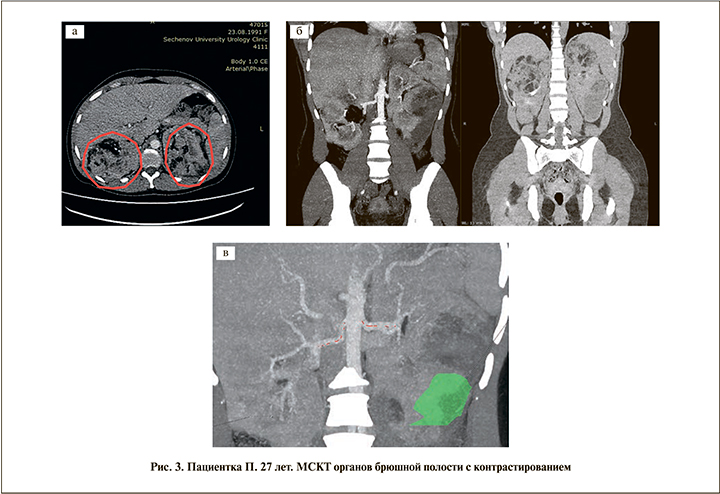

Данные мультиспиральной КТ (МСКТ) брюшной полости с контрастированием (04.07.2019): почки увеличены за счет наличия множественных ангиомиолипом классического типа; размер правой почки – 96×101×209 мм, левой – 80×107×225 мм (рис. 3, а)). Правая почка: наибольшая ангиомиолипома классического типа определяется в верхнем сегменте – 92×76×73 мм.

Левая почка: наибольшие ангиомиолипомы классического типа определяются в верхнем (97×73×83 мм) и заднем (71 мм в диаметре) сегментах. Определяется подкапсульная и паранефральная гематомы на уровне заднего и нижнего сегментов левой почки по причине разрыва ангиомиолипомы заднего сегмента; ориентировочный объем – 101 мл (рис. 3, б). Прослеживается по одной почечной артерии с каждой стороны с наличием бифуркаций на уровне ворот почек; артериовенозной мальформации не выявлено (рис. 3, в).

По данным МРТ, признаков продолжающегося кровотечения нет (рис. 4).